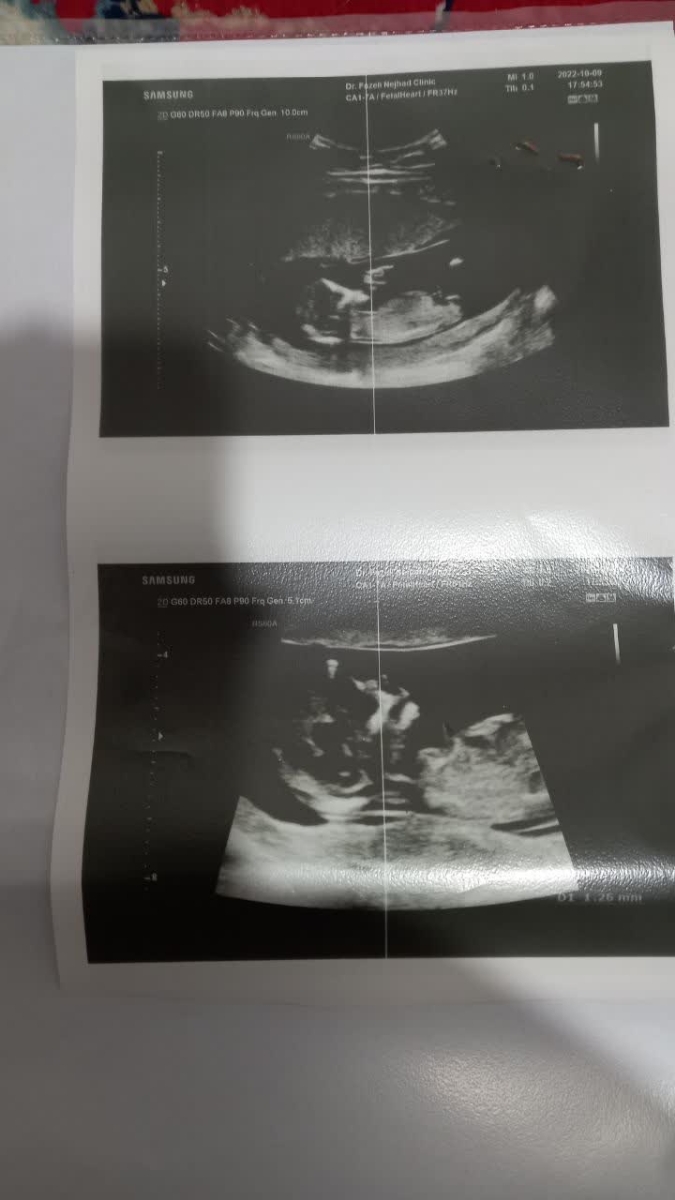

سلام و درود خدمت پرشک اوما و دوستان عزیز اومایی. این سونو و آزمایش یکی از دوستانم هست. میشه لطفا یه نگاهی بهش بندازید ببینین مشکلی داره یا نه و یا اگر ریسک داره ریسکش چقدر بالاست؟

در سونوگرافی انجام شده برای شما همه چیز خوب است و در غربالگری شما، ریسک محاسبه شده برای تریزومی ۱۸ و 13 در محدوده کم خطر قرار دارد اما در مورد تریزومی 21 یعنی سندروم داون، ریسک محاسبه شده اگرچه مثبت و پرخطر نیست، اما در محدوده حد وسط قرار دارد. به بیانی اگر 495 خانم و مادر باردار مشابه به شرایط شما باشند، فرزند یک نفر از بیمار و فرزند مابقی سالم است. اگرچه این رقم به نظر ناچیز است اما در علم پزشکی و باتوجه به اینکه بیماری داون درمان پذیر نیست، اهمیت بسیار زیادی دارد و بنابراين در صورت صلاحدید پزشکتان باید بررسی های تکمیلی انجام شوند تا مطمئن شویم که کوچولوی شما سالم است. باتوجه به بالا بودن سطح Mom مارکر بتا، بهتر است سل فری دی ان ای یا همان nipt انجام شود ، به علاوه در سه ماهه دوم سونوگرافی کالر داپلر عروق جفتی انجام شده و در صورت موافقت پزشکتان آسپرین آغاز گردد. تصمیم گیری نهایی در مورد نوع بررسی مورد نیاز با پزشک شما است تا خیالمان از هر جهت راحت شود 💞💞💞